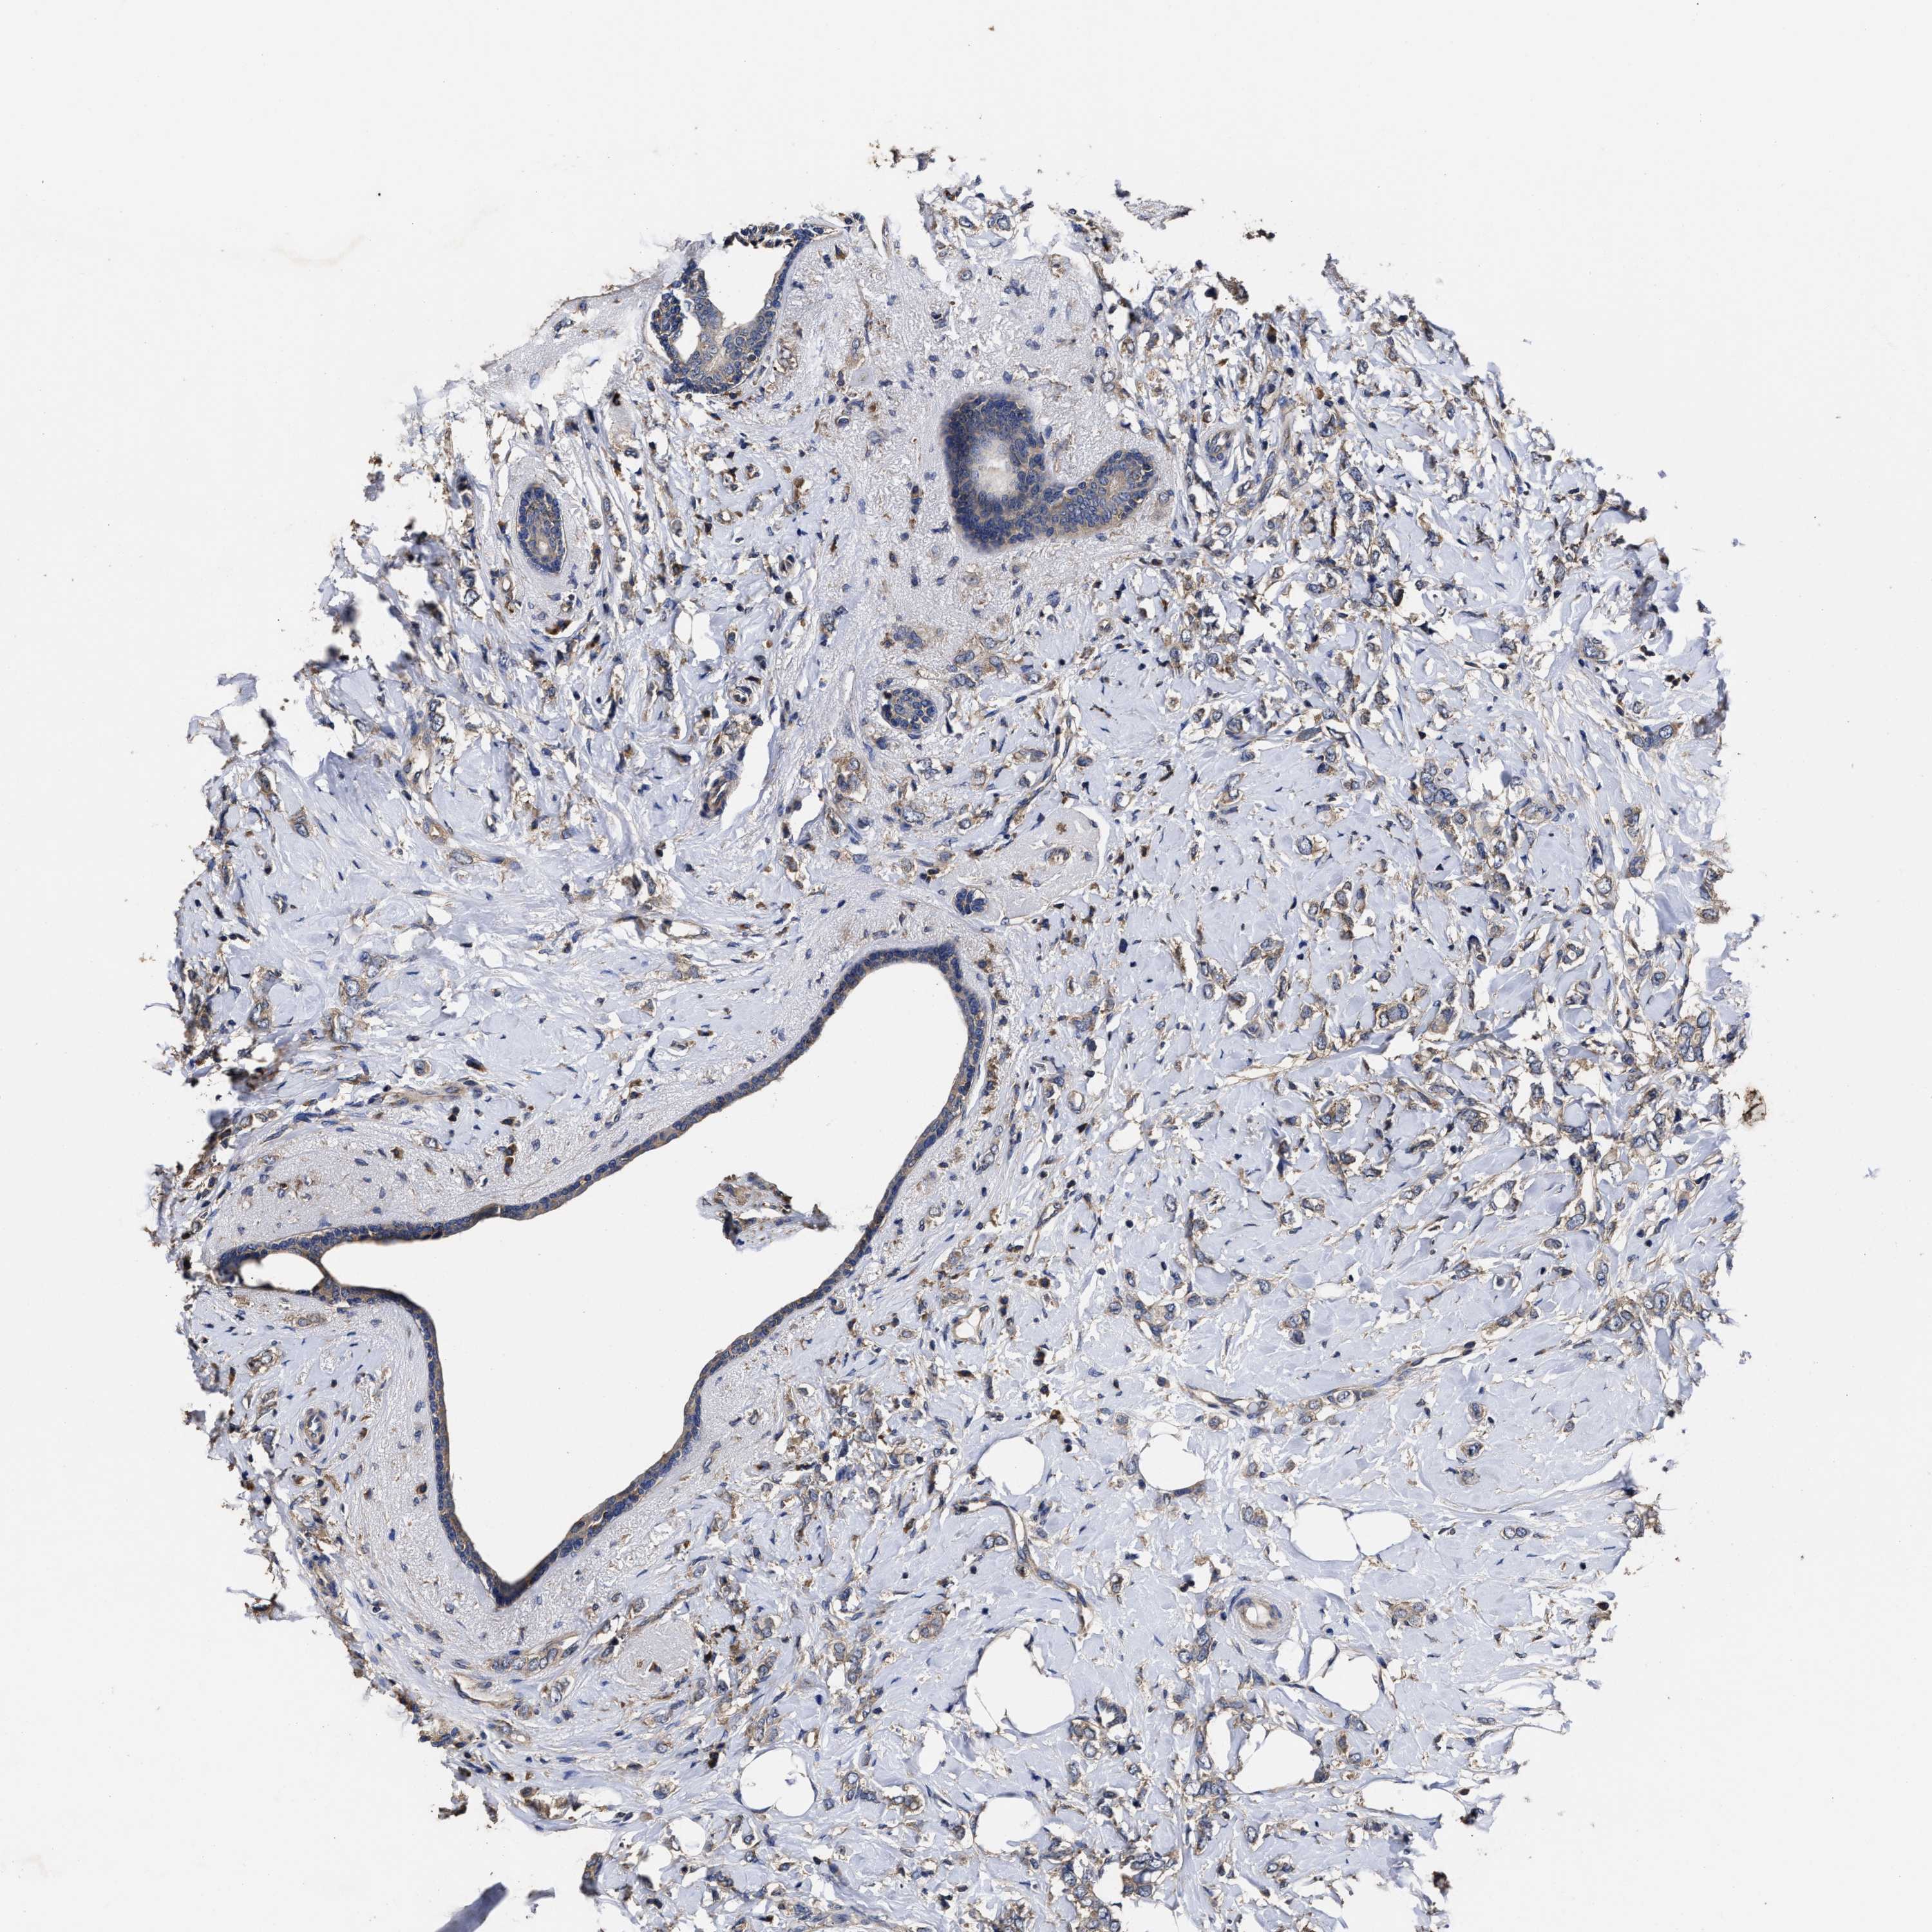

CANCER BREAST CANCER Show tissue menu

BRCA TCGA BRCA VALIDATION PROTEIN EXPRESSION